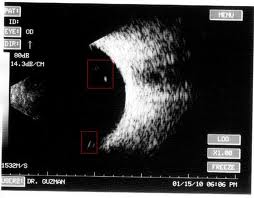

Ecografia

Es un estudio complementario mediante el cual se puede evaluar la parte posterior del ojo. Del cristalino hacia atras, ya sea vitreo, retina, esclera, nervio optico e incluso la orbita.

La ecografia trabaja por ultrasonido. Sirve para aquellos casos en que no hay transparencia de medios, como por ejemplo una catarata completa, y necesitamos saber si la retina esta aplicada en su posicion correcta para decidir si operar o no dicha catarata.

Tambien se usa para evaluar tumores oculares en aquellos casos sin trasparencia de medios.